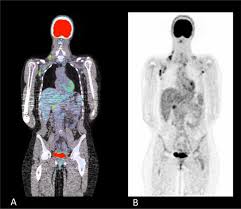

Tumor necrosis factor receptor associated periodic syndrome. Its most severe manifestation is secondary amyloidosis. Tumor necrosis factor receptor-associated periodic syndrome commonly known as TRAPS is a condition characterized by recurrent episodes of fever. This study examined the diagnostic pathway and treatments at tertiary centers for familial Mediterranean fever FMF tumor necrosis factor receptor-associated periodic syndrome TRAPS and mevalonate kinase deficiency MKDhyperimmunoglobulinemia D syndrome HIDS.

Tumor necrosis factor TNF receptor-associated periodic syndrome TRAPS is an autosomal dominant autoinflammatory disorder characterized by periodic fever episodes arthralgia myalgia abdominal pain serositis and skin rash. Fevers can occur anywhere between every 6.